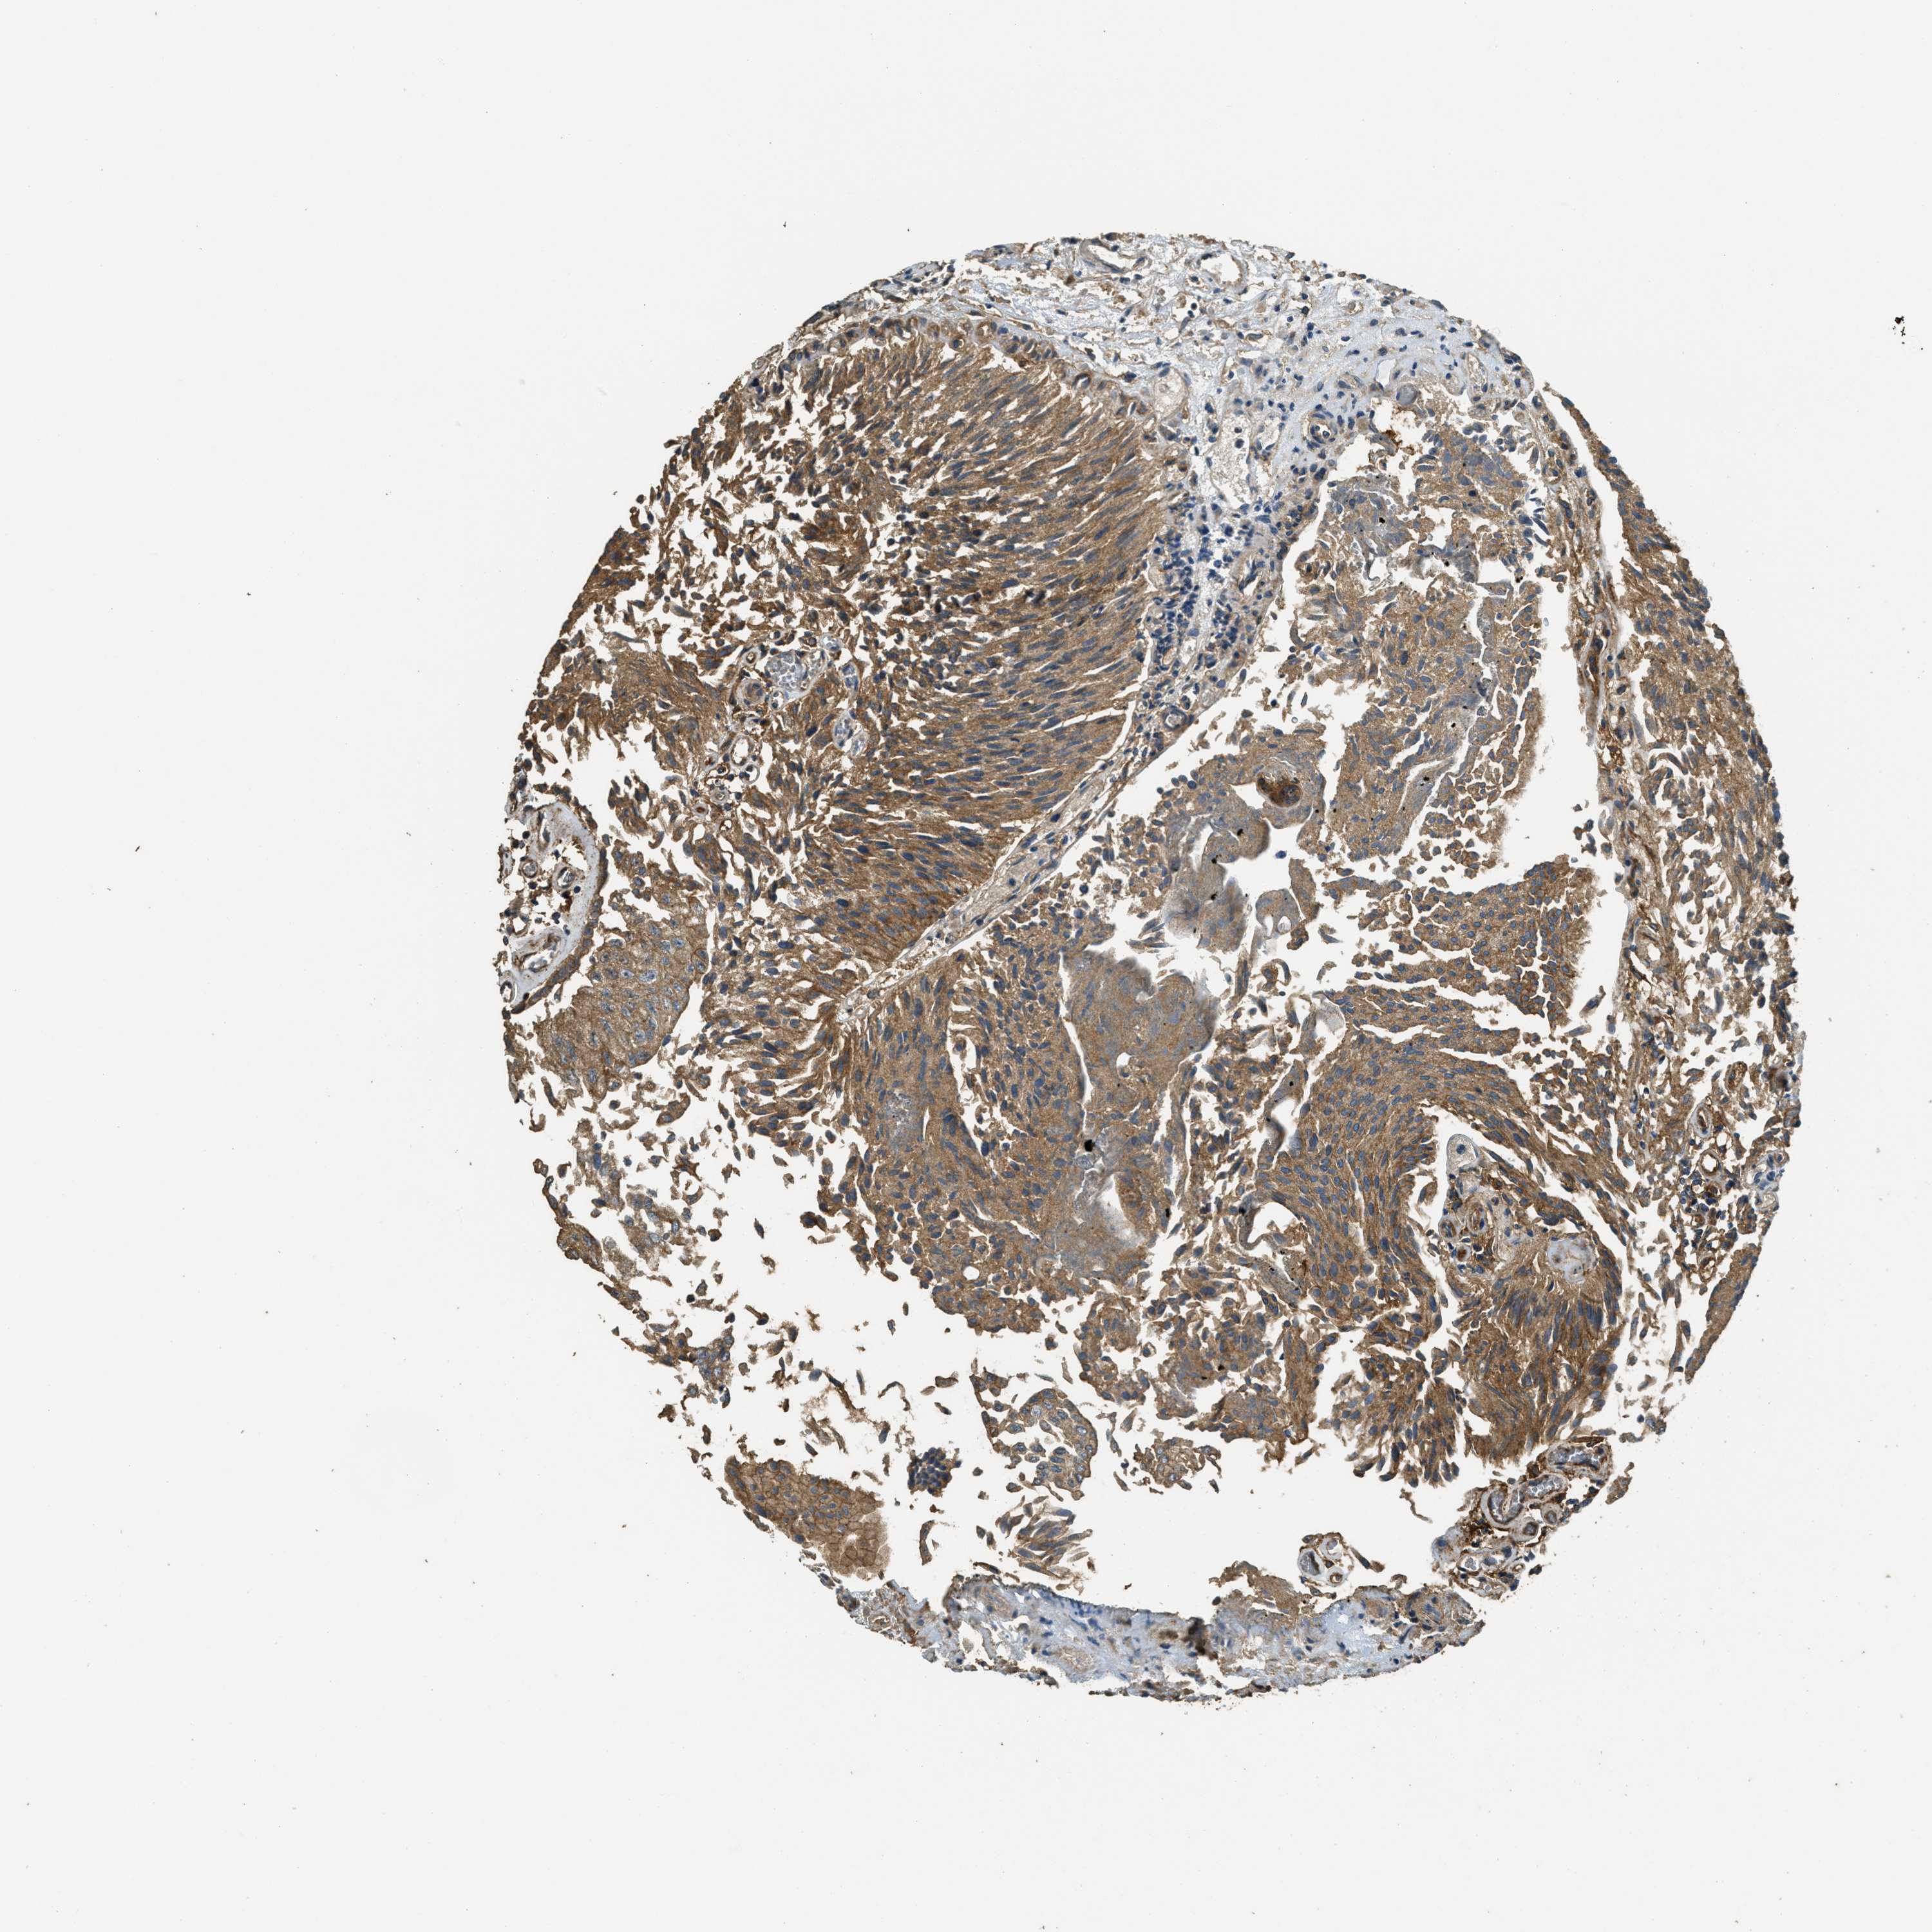

UROTHELIAL CANCER - Protein expressioni

A mouse-over function shows sample information and annotation data. Click on an image to view it in a full screen mode. Samples can be filtered based on level of antibody staining by selecting one or several of the following categories: high, medium, low and not detected. The assay and annotation is described here.

Note that samples used for immunohistochemistry by the Human Protein Atlas do not correspond to samples in the TCGA dataset.

Antibody stainingi

Antibody staining in the annotated cell types in the current human tissue is reported as not detected, low, medium, or high, based on conventional immunohistochemistry profiling in selected tissues. This score is based on the combination of the staining intensity and fraction of stained cells.

Each image is clickable and will lead to virtual microscopy that enables deeper exploration of all samples and also displays staining intensity scores, fraction scores and subcellular localization as well as patient and tissue information for each sample.

Antibody HPA009285

Antibody HPA017139

Antibody CAB017826

Staining

High

Medium

Low

Not detected

Intensity

Strong

Moderate

Weak

Negative

Quantity

>75%

75%-25%

<25%

None

Location

Nuclear

Cytoplasmic/membranous

Cytoplasmic/membranous,nuclear

Urothelial carcinoma, Low grade

Urothelial carcinoma, High grade